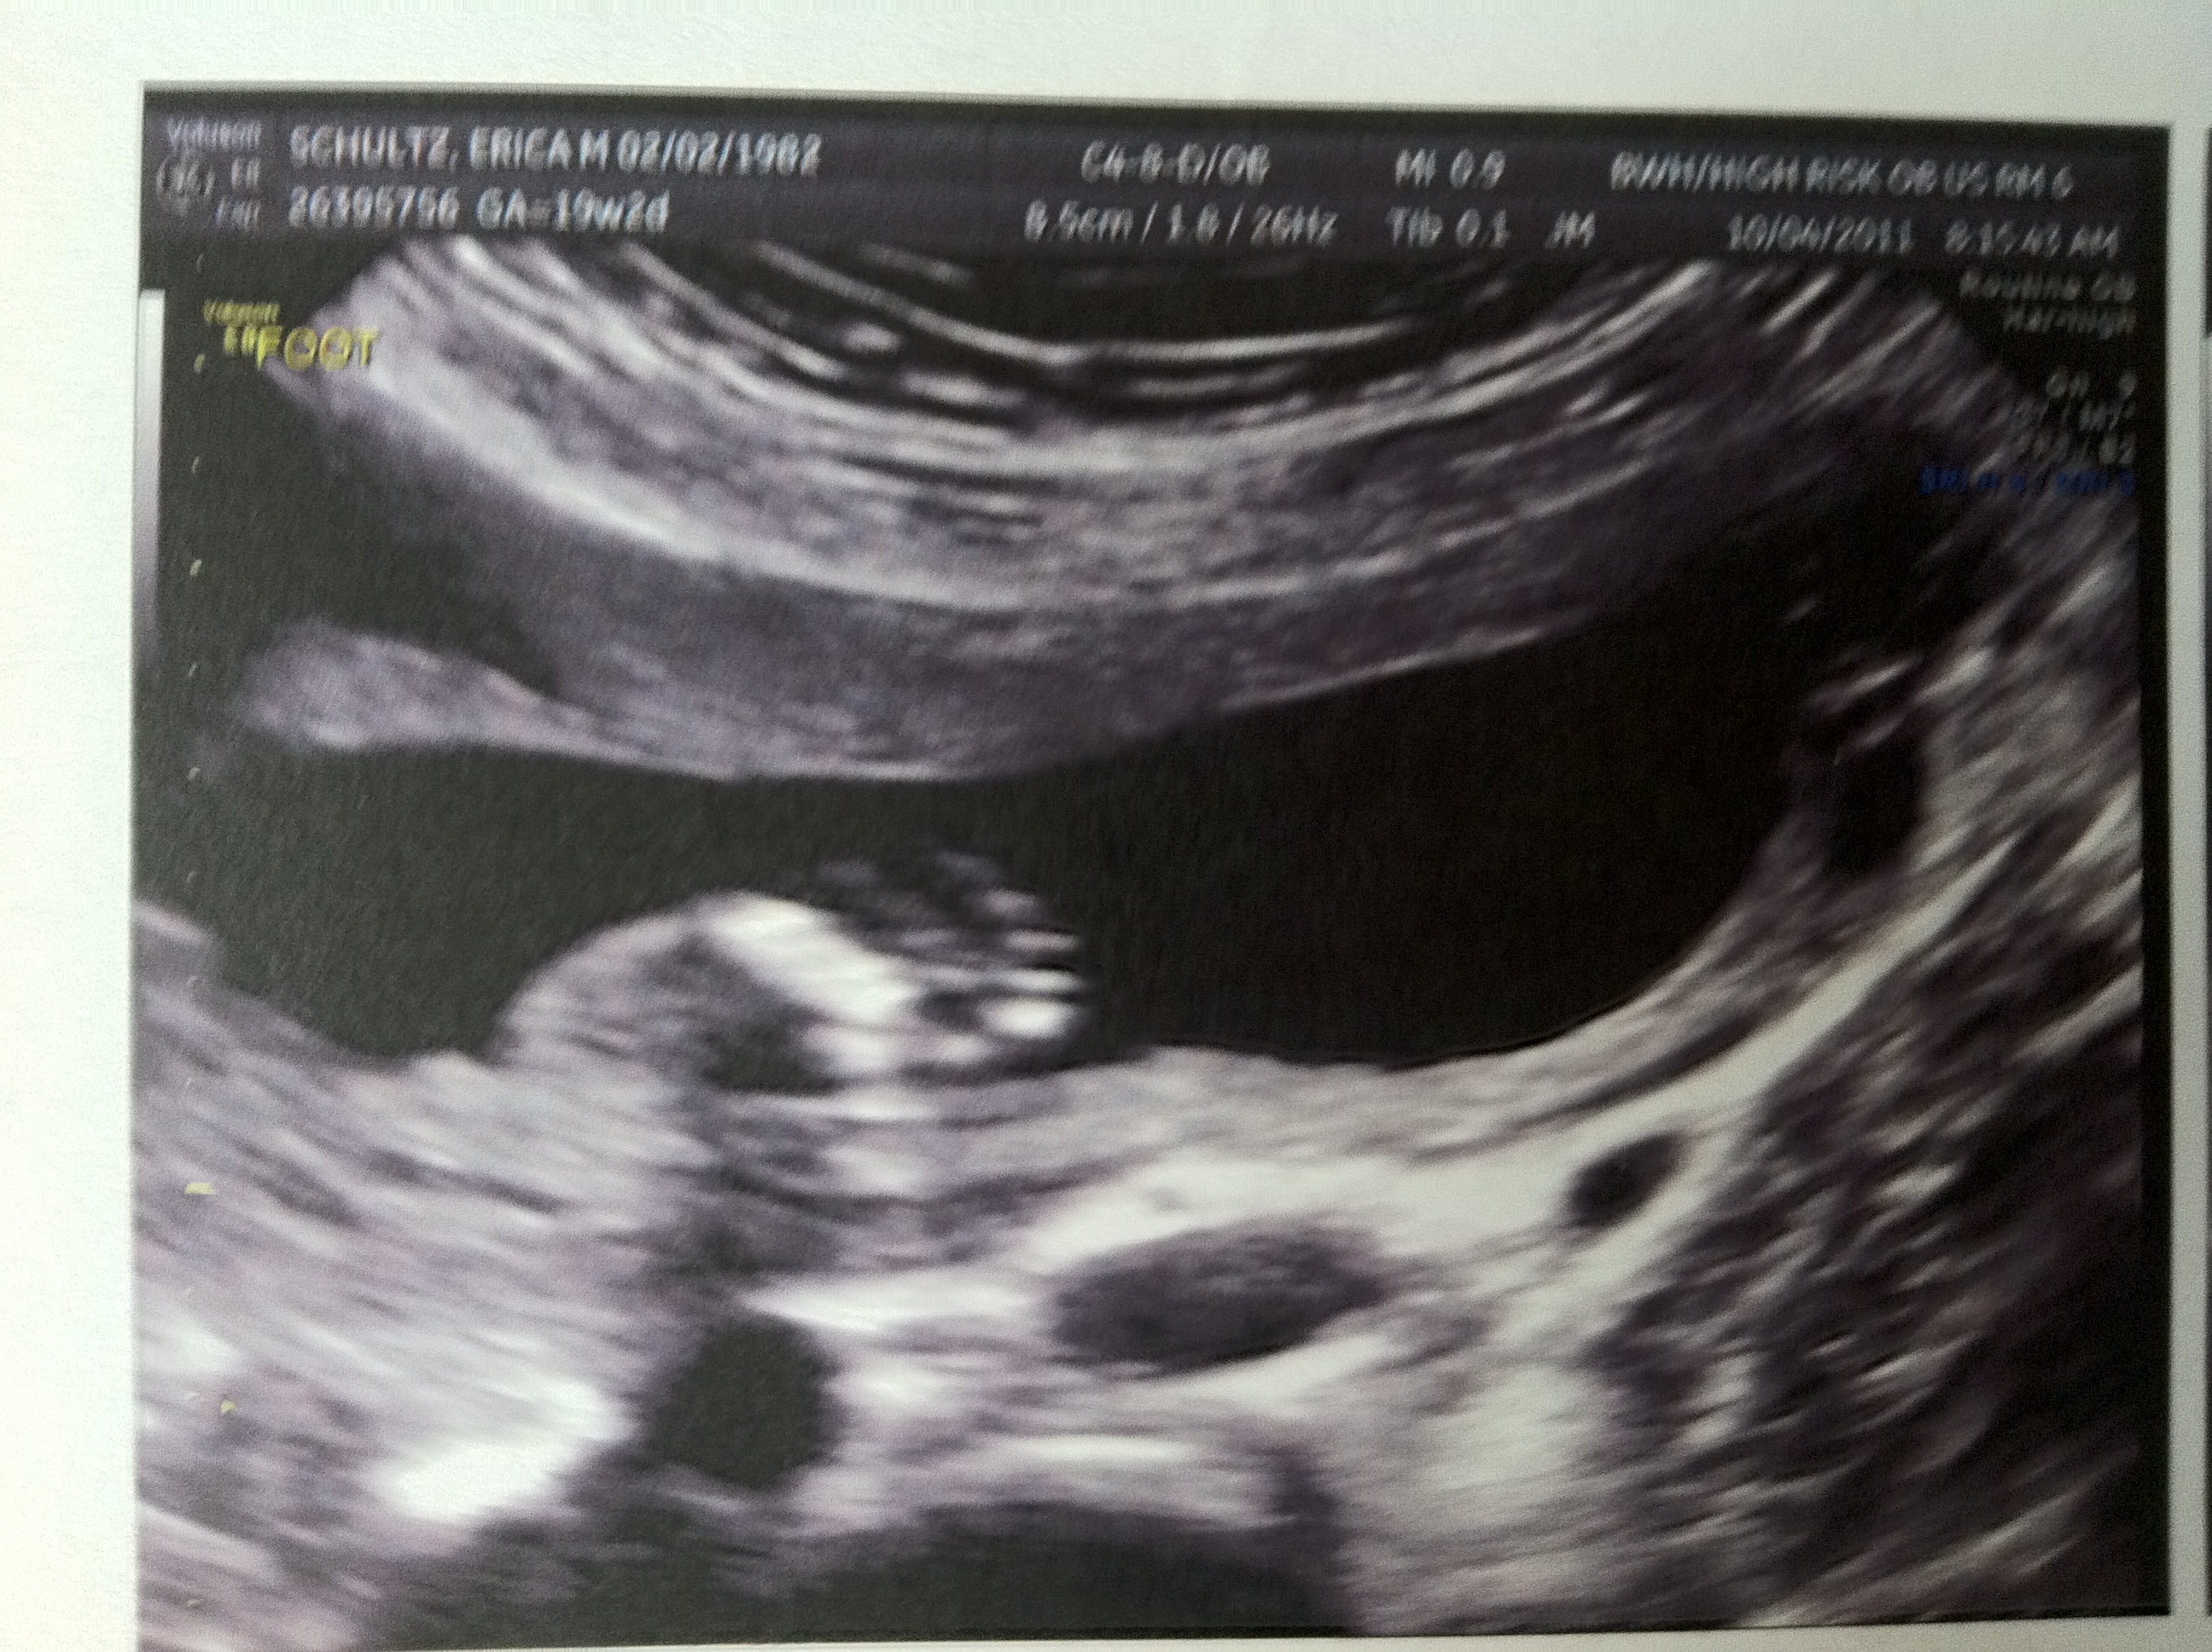

I have Mommy’s Fingers and Toes!